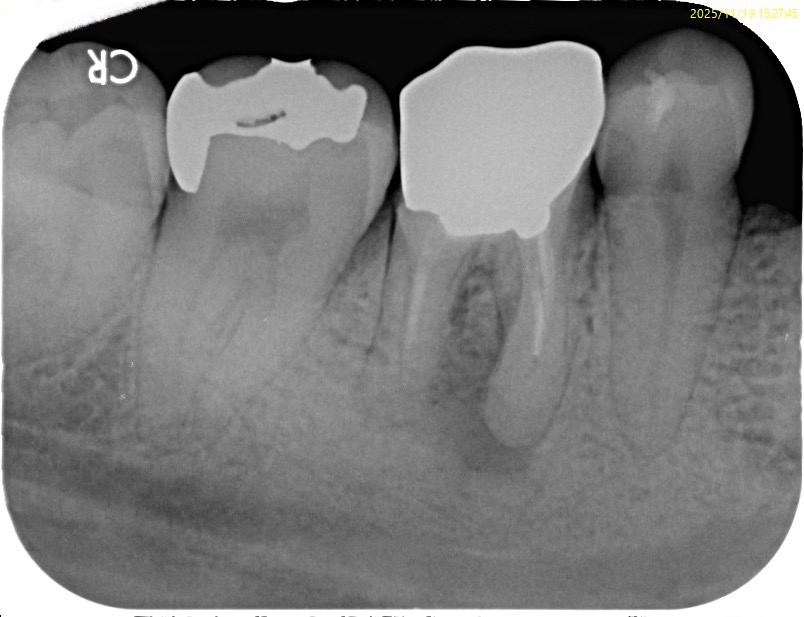

右下6番歯根端切除術

治療前

黒い部分は、骨が無くなっていることを意味する。

遠心まで病変が広がっているが、これは近心根の病変によるものであろう。